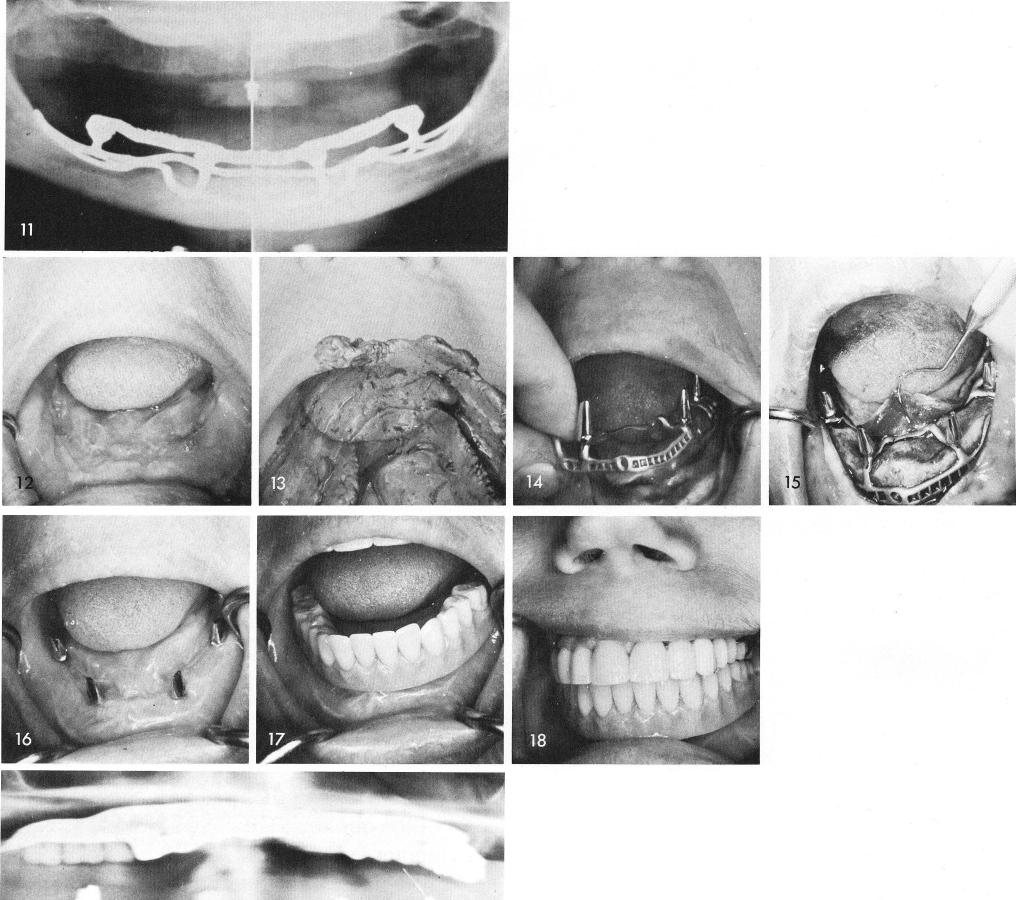

tains four, 360° circumferential clasps that can be adjusted over the posts of the subperiosteal implant, figs. 9, 10. A post-operative x-ray shows the accurate fit, fig. 11.

Even with extremely concave situations as seen clinically, fig. 12, the rubber base impression reveals good bone height, fig. 13, for a properly designed implant, fig. 14, to fit with great accuracy and retention over the atrophied mandibular bone, fig. 15. Very often, in order to obtain healing such as was obtained in this case accessory labial and buccal incisions had to be made to the periosteum. Some of the scar tissue seen here is from the accessory incisions, fig. 16. The implant denture is implant borne and does not touch the tissues, figs. 17, 18. The post-operative x-ray, fig. 19.